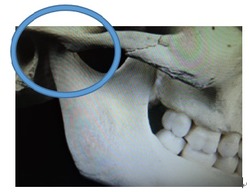

この写真の顎関節は小学校低学年の形です。

この時期は顎関節がまだ固まっていない為に自由に下顎の位置を変える事が出来ます。

受け口の治療には良い時期と考えられます。

出っ歯の治療は咬み合わせの基礎を作りやすい時期と考えて下さい。